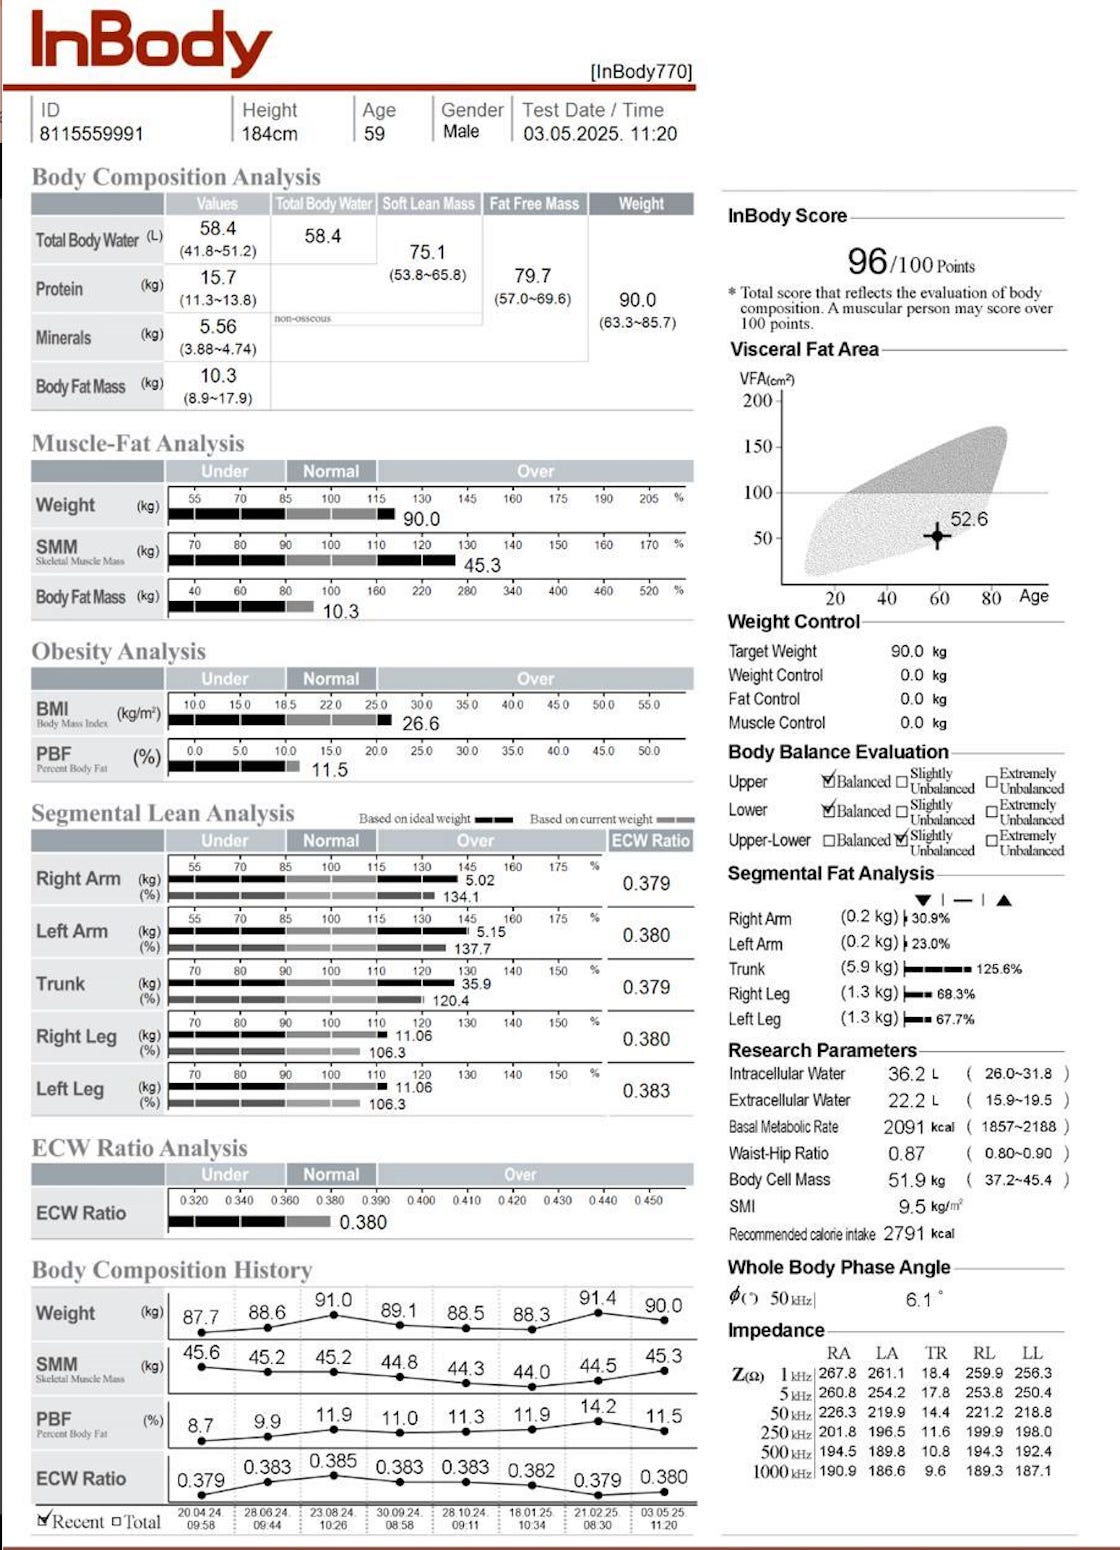

Género: Masculino + Edad 59 años + Estatura: 1.84cm

Objetivos:

Longevidad y cuerpo atlético

Esto significa: Mantener un porcentaje de grasa óptimo y tener una masa muscular adecuada que le permita ser ágil y fuerte a lo largo del tiempo.

Su problemática:

Solo no estaba haciendo el ejercicio adecuado para su edad y faltaba más orden en su alimentación.

También necesitabamos optimizar su digestión para que absorbiera mejor proteínas por que en ciertos biomarcadores marcaba pobre absorción.

Optimizar su sueño sobretodo el sueño profundo.

¿Que le puede mermar este proceso?

A él en si la edad nomás. Es muy disciplinado, orientado a los detalles y muy constante con su alimentación, ejercicio y suplementación.

Sus temas digestivos

La falta de sueño restaurativo

¿Cómo se ven los resultados del inbody?

En sí muy bien buscamos que este entre 10 y 12% de grasa y estamos promoviendo más masa muscular de 46 kilogramos. Vamos en buen camino.

Conclusiones de su caso y acciones a seguir llevando a cabo:

Si el se mantiene entre 10 y 12% de grasa es ideal. No se siente bien abajo de eso ni más alto que eso. Subimos a 14.2 recientemente pero fue porque se salio de su alimentación y rutina porque viajo. Le subió más a las calorías en total y a los carbos pero ya regreso a su rutina y luego luego se acomodo de nuevo con su composición corporal donde se siente cómodo.

Estamos buscando llegar a 46 a 47 kg de masa muscular. Ahí vamos solo necesitamos seguir con el consumo adecuado de proteína para el y que absorba adecuadamente por eso trabajamos un protocolo enzímatico de absorción de proteínas especifico

Extra empeño en la sobrecarga progresiva al momento de hacer fuerza.

También para lograr este pico muscular tenemos que seguir mejorando su sueño que en eso estamos trabajando en particular porque es lo único que nos falta optimizar porque duerme abajo de las 7 horas y no duerme corrido.